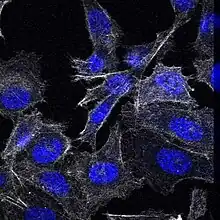

PC3 cells have low testosterone-5-alpha reductase and acidic phosphatase activity, and do not express PSA (prostate-specific antigen). Furthermore, karyotypic analysis has shown that PC3 are near-triploid, having 62 chromosomes. Q-band analysis showed no Y chromosome. From a morphological point of view, electron microscopy revealed that PC3 cells show characteristics of a poorly-differentiated adenocarcinoma. They have features common to neoplastic cells of epithelial origins, such as numerous microvilli, junctional complexes, abnormal nuclei and nucleoli, abnormal mitochondria, annulate lamellae, and lipoidal bodies.